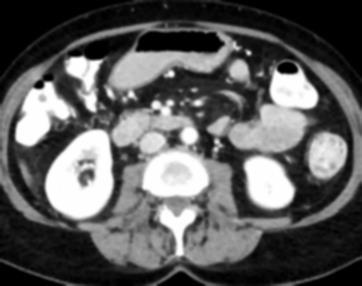

Due to the constraints of the imaging device and high cost in operation time, computer tomography (CT) scans are usually acquired with low intra-slice resolution. Improving the intra-slice resolution is beneficial to the disease diagnosis for both human experts and computer-aided systems. To this end, this paper builds a novel medical slice synthesis to increase the between-slice resolution. Considering that the ground-truth intermediate medical slices are always absent in clinical practice, we introduce the incremental cross-view mutual distillation strategy to accomplish this task in the self-supervised learning manner. Specifically, we model this problem from three different views: slice-wise interpolation from axial view and pixel-wise interpolation from coronal and sagittal views. Under this circumstance, the models learned from different views can distill valuable knowledge to guide the learning processes of each other. We can repeat this process to make the models synthesize intermediate slice data with increasing inter-slice resolution. To demonstrate the effectiveness of the proposed approach, we conduct comprehensive experiments on a large-scale CT dataset. Quantitative and qualitative comparison results show that our method outperforms state-of-the-art algorithms by clear margins.